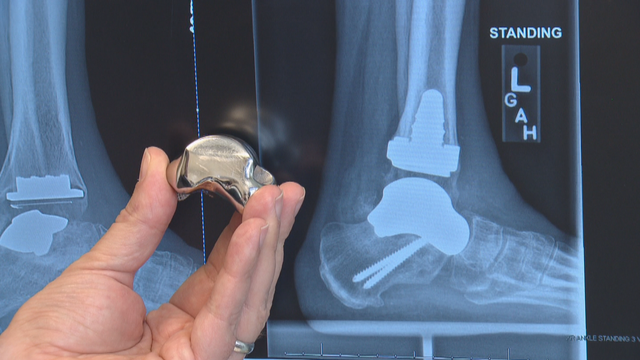

Using a CT scan of Dee Dee's right talus bone, Additive Orthopaedics in New Jersey created a custom, 3D printed talus made of cobalt chrome and titanium.

"It was created for her ankle, for her anatomy," said Hunt.

It has titanium mesh on the bottom.

"Bone can actually fuse to it," he said.